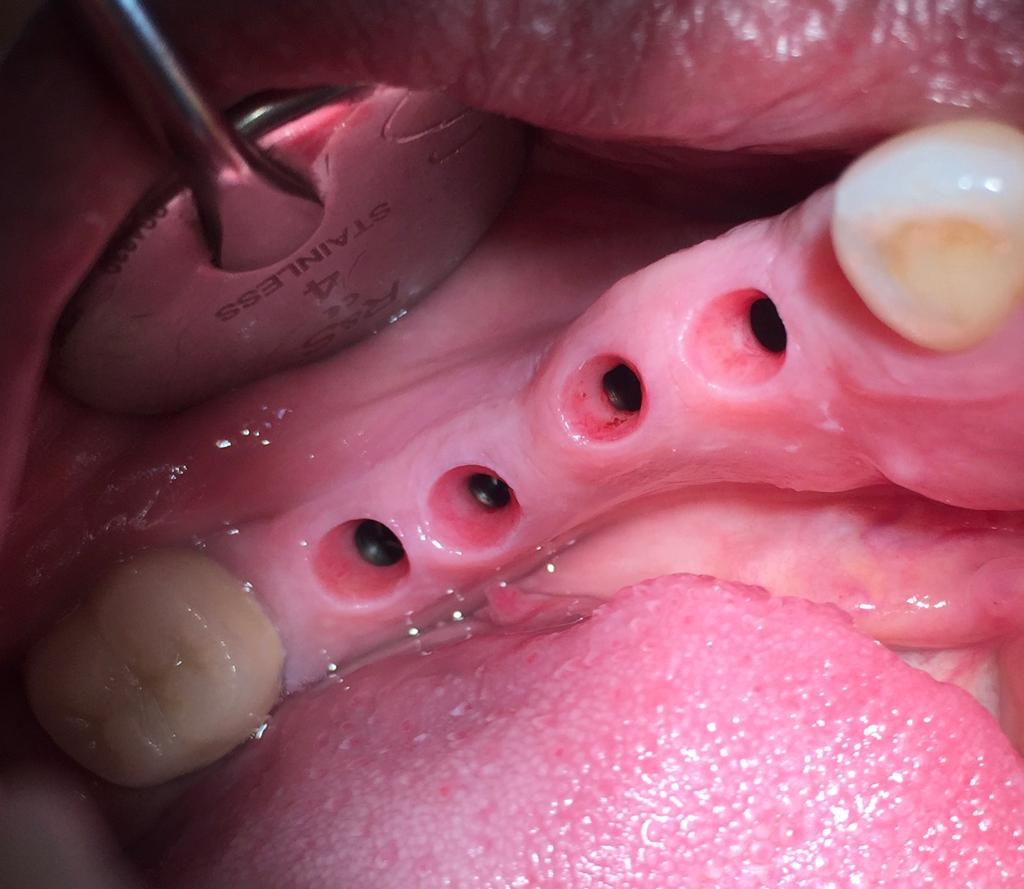

2éme TEMPS

CHIRURGICAL